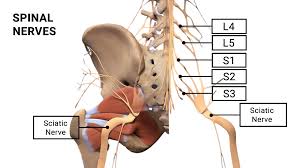

Download Sciatic nerve pain pictures